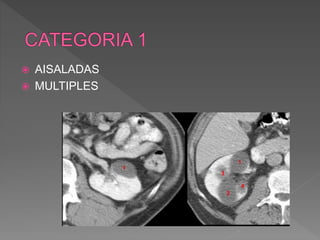

 AISALADAS

 MULTIPLES

 Redondeadas paredes lisas regulares,

 Densidad homogenena

 No refuerzo con contraste

 Menores 3cm, asintomaticas, o grandes volumenes ,

comprimen estructuras vecinas, obstruccion del sist.

Colector ,hematuria